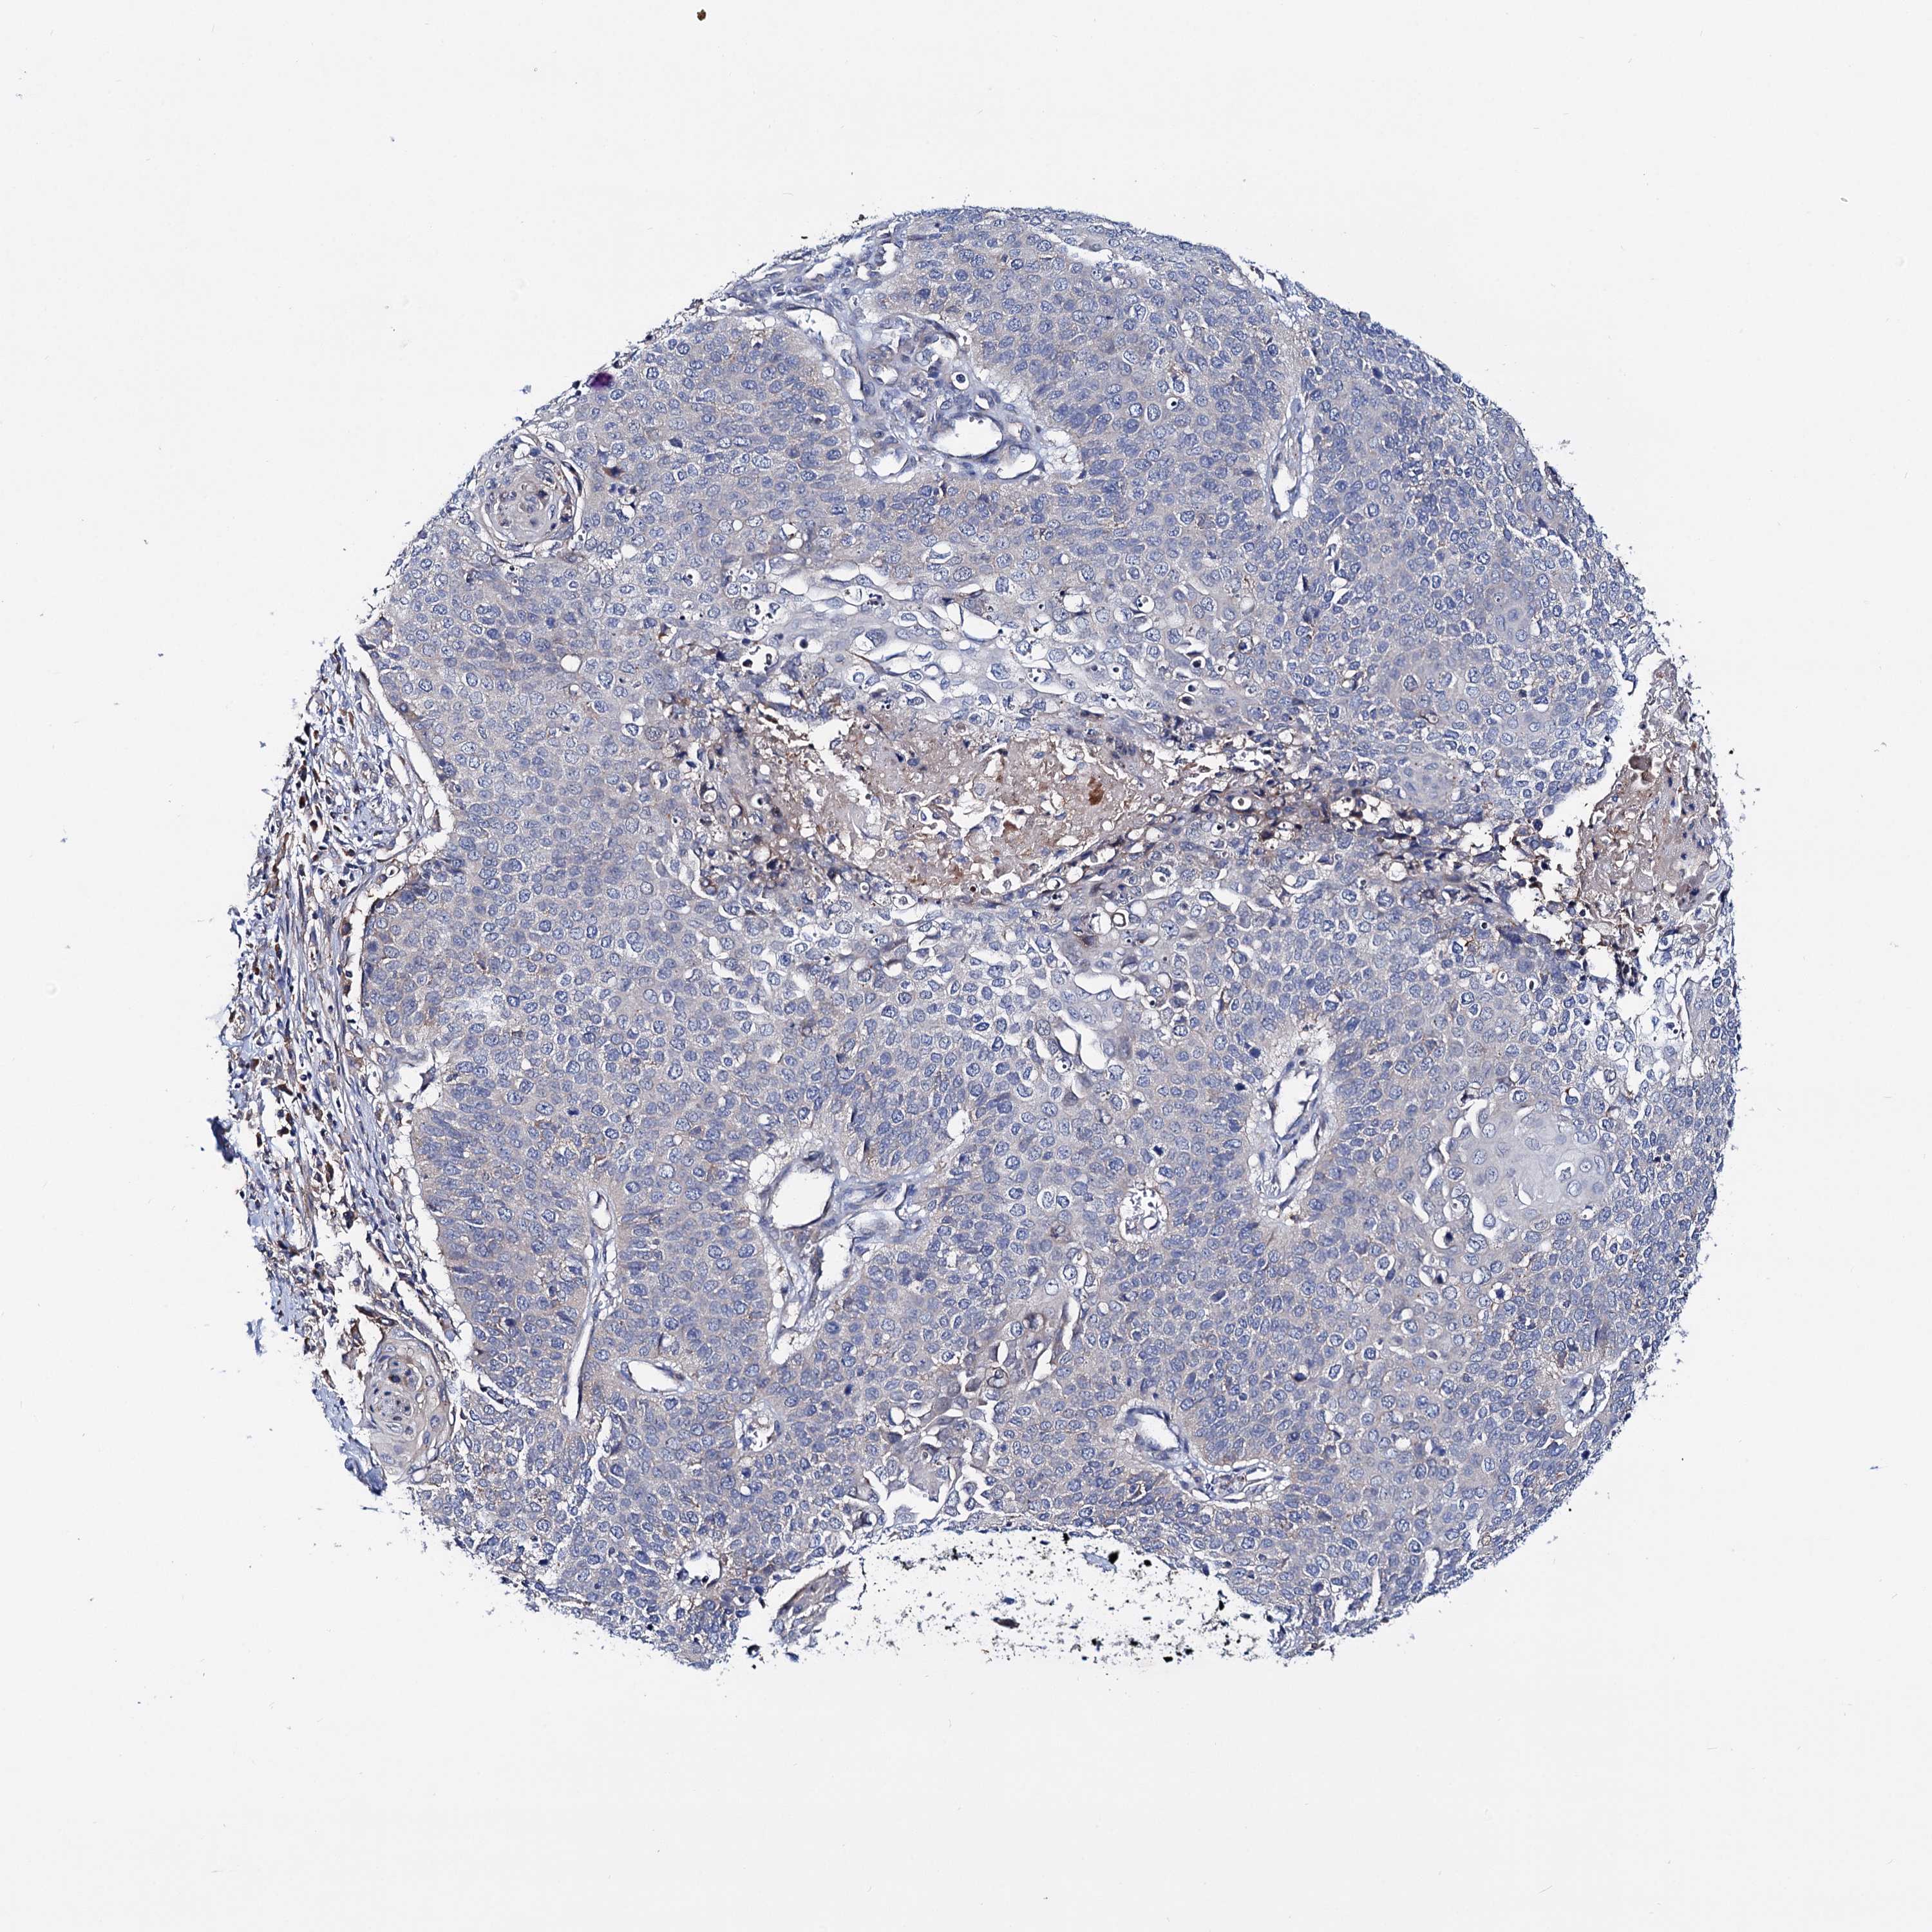

CERVICAL CANCER - Protein expressioni

A mouse-over function shows sample information and annotation data. Click on an image to view it in a full screen mode. Samples can be filtered based on level of antibody staining by selecting one or several of the following categories: high, medium, low and not detected. The assay and annotation is described here.

Note that samples used for immunohistochemistry by the Human Protein Atlas do not correspond to samples in the TCGA dataset.

Antibody stainingi

Antibody staining in the annotated cell types in the current human tissue is reported as not detected, low, medium, or high, based on conventional immunohistochemistry profiling in selected tissues. This score is based on the combination of the staining intensity and fraction of stained cells.

Each image is clickable and will lead to virtual microscopy that enables deeper exploration of all samples and also displays staining intensity scores, fraction scores and subcellular localization as well as patient and tissue information for each sample.

Antibody HPA038793

Antibody HPA053691

Staining

High

Medium

Low

Not detected

Intensity

Strong

Moderate

Weak

Negative

Quantity

>75%

75%-25%

<25%

None

Location

Nuclear

Cytoplasmic/membranous

Cytoplasmic/membranous,nuclear

Squamous cell carcinoma, NOS

Adenocarcinoma, NOS